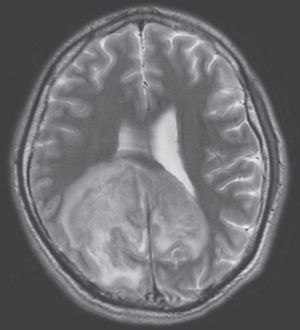

A 31-year-old man from El Salvador, recently diagnosed with HIV/AIDS, presented to the emergency department with headache, confusion, gait instability, and fever. Brain MRI showed a large mass in the right parietal and occipital lobes. Brain aspirate identified Trypanosoma cruzi. What vector is likely responsible for transmission of this protozoa to this patient? a) Anopheles mosquito b) Triatomine bug c) Ixodes tick d) Phlebotomine sand fly e) Tsetse fly Source: nejm.org